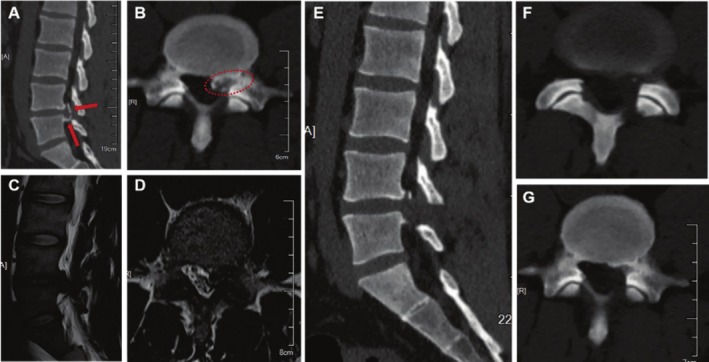

Methods: A total of 271 patients who suffered from single CLDH (97 patients) or NCLDH (non-calcified lumbar disc herniation) who received PEID surgery between January 2016 and December 2018 in our hospital participated in this retrospective study. Moreover, CLDH was divided into four grades based on preoperative sagittal CT images, including 34 Grade I, 22 Grade II, 19 Grade III, and 22 Grade IV. Operative time was evaluated between the two groups. In addition, VAS (leg pain), ODI, and MacNab scale score were applied to assess the efficacy of PEID in treating CLDH with different calcification degrees by Student's t tests or χ2 test.

Results: All the patients successfully underwent PEID surgery. According to the analysis, the operative time in the CLDH group was significantly longer than that in NCLDH group. Preoperative and postoperative VAS (leg pain) and ODI scores have no significant differences between the CLDH and NCLDH groups. Furthermore, postoperative modified MacNab scale scores and complication rates were almost the same in the two groups. However, there were some differences in terms of VAS (leg pain), ODI, and MacNab scores during LDH patients with different degrees of calcification. CLDH was divided into four grades in our study, and the analysis displayed that VAS (leg pain) and ODI scores after operation in the Grade IV CLDH group were both obviously higher than those in the control group. Moreover, the modified MacNab scale showed that excellent or good rates in the Grade IV CLDH group (73%) were lowest, and they were significantly lower than those in the control group (91%). The other statistical indexes such as recurrence and complication rates showed no significant difference in CLDH with different degrees of calcification.